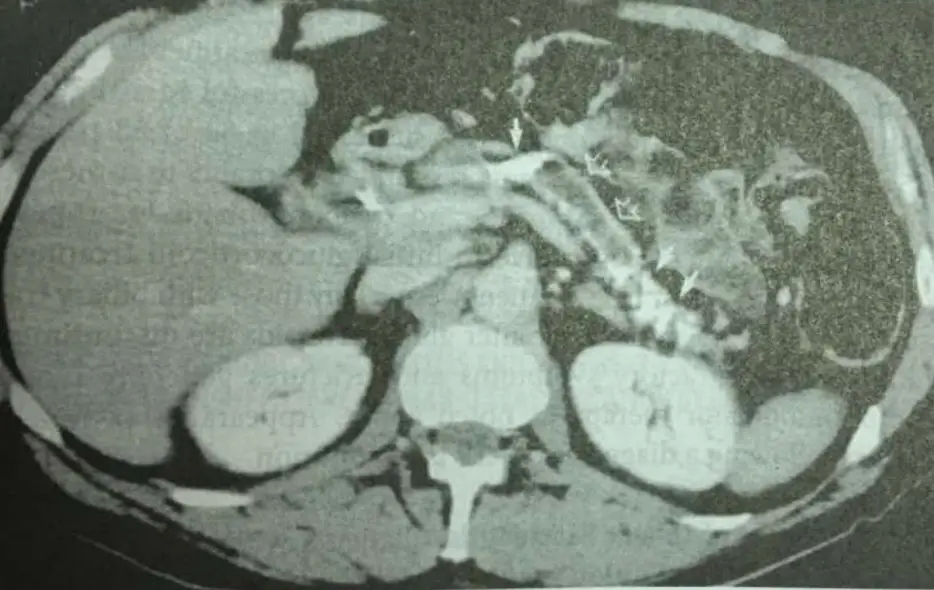

68歲男性有酗酒病史,因間歇性腹痛合併腹瀉7個月至急診,病患並未服用任何藥物。身體檢查並無發燒,BP:108/72mmHg、脈搏:80/min、呼吸16/min,肚子並無壓痛也未有腹脹。血液檢查AST:155U/L、ALT:88U/L、ALP:96U/L、Bilirubin(total):1.1mg/dL、amylase:65U/L、lipase:70U/L。糞便檢查有脂肪,腹部電腦斷層如圖,下列何者為正確治療? 圖片描述

慢性酗酒相關慢性胰臟炎造成胰臟外分泌功能不全(exocrine pancreatic insufficiency, EPI),導致脂肪吸收不良及脂肪瀉(steatorrhea);影像可見胰臟鈣化及胰管擴張;治療首選胰臟酵素補充。

腹部電腦斷層顯示胰臟實質內多發粗大鈣化灶,胰管呈不規則擴張,符合慢性胰臟炎晚期影像特徵(parenchymal/ductal calcifications 最具特異性,可見於約50%個案,胰管擴張約68%)(pmc.ncbi.nlm.nih.gov);鈣化常散佈於胰頭及胰體部,代表長期發炎後纖維化與石灰化形成,臨床上即可能出現胰外分泌不足症狀。